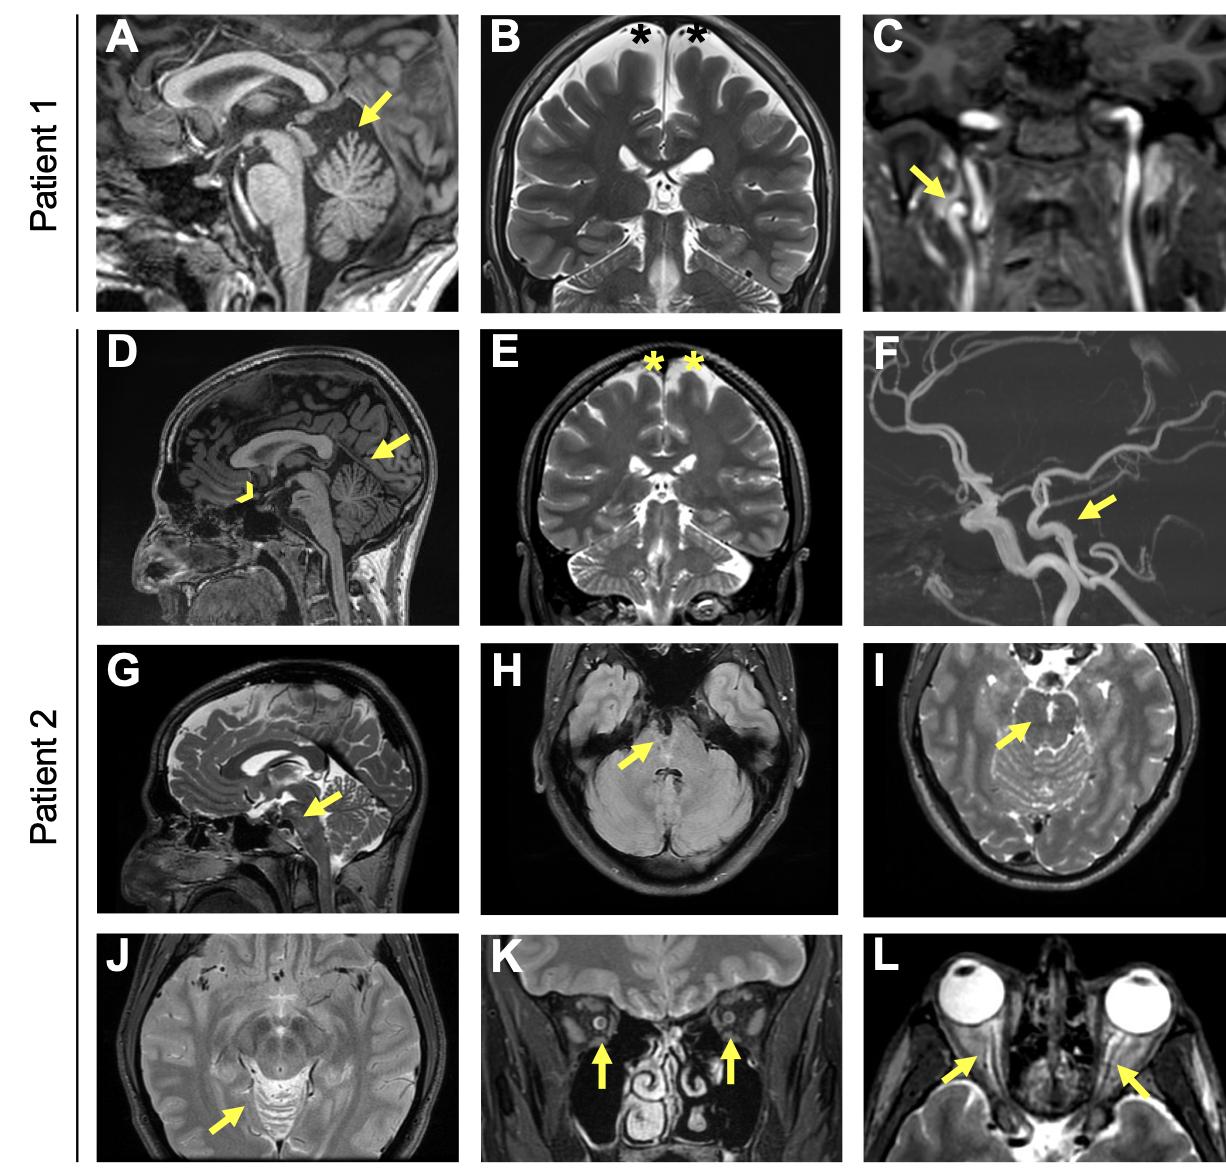

Supplemental Figure 2. Cerebral MRI of Patients 1 and 2. A) Sagittal T1 weighted MRI images showing cerebellar atrophy involving specifically the superior part of the cerebellar vermis (arrow). The pituitary gland is normal both for the anterior and the posterior part. B) Coronal T2 weighted images showing diffuse widened subarachnoid spaces suggesting mild cerebral atrophy (black asterisks). C) Coronal T1 weighted imaging showing loop of the cervical segment of the right internal carotid artery, which is an unusual finding in young adults (arrow). D) Sagittal T1-weighted images showing cerebellar atrophy involving specifically the superior part of the cerebellar vermis (arrow). The pituitary gland is normal both for the anterior and the posterior part (arrowhead). E) Coronal T2 weighted images showing diffuse widened subarachnoid spaces suggesting mild cerebral atrophy (asterisks). F) 3D Time of Flight images showing the dolichoectasia of the basilar artery (arrow). G) Sagittal T2 weighted images showing the slight brainstem compression (arrow). H) Axial Fluid Attenuated Inversion Recovery T2 weighted images showing the dolichoectasic basilar trunk in a mid- pons cleft (arrow). I) Axial T2 weighted images showing stretched enlarged perivascular spaces in the mid-pons (arrow). J) Axial T2 weighted images showing the atrophic superior vermis (arrow). Coronal (K) and axial (L) T2 weighted images showing bilaterally enlarged perioptic fluid space in the intraconic and pre-bulbar tracts (arrows). |